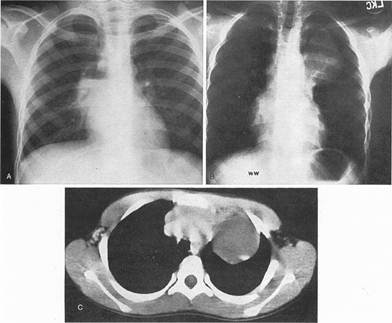

Мал.17. А.бронхогенна, центрально розташована кіста, що сполучається з бронхом, про що говорить рівень рідини.

В.Центральна кіста не сполучена з бронхом (немає рівня рідини).

С.Центральна кіста (В) на КТ.

Мал.18. Вроджена кіста правої легені, що наповнена рідиною.

Мал.19. Напружена повітряна кіста правої легені. Медіастінальна грижа.